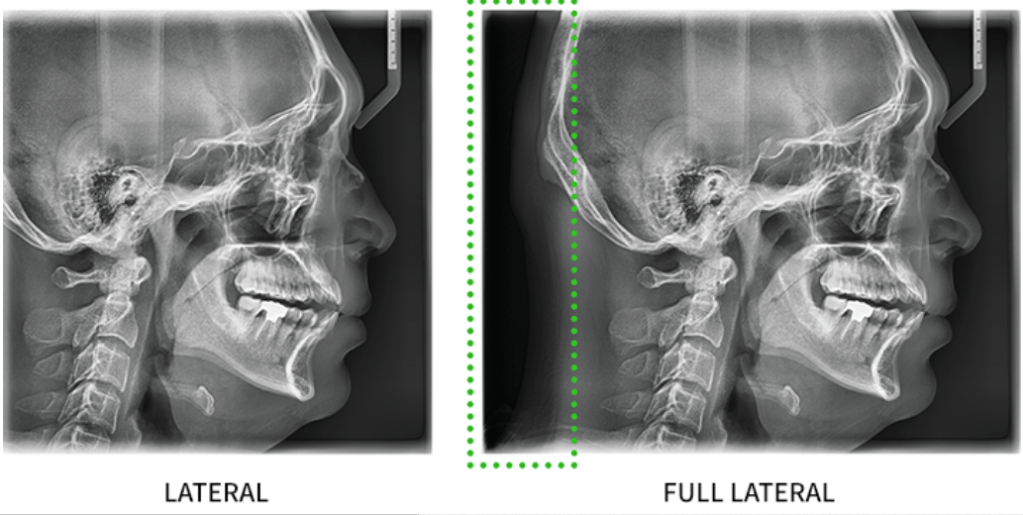

3. ด้วยเทคโนโลยี Magic Pan ทำให้ได้ภาพ panoramic ที่ชัดเจนทุกมุมมอง เมื่อเทียบกับ ภาพ x-ray panoramic ทั่วๆไป โดยเฉพาะบริเวณฟันหน้า และ บริเวณมุมของขากรรไกร และ คลองรากฟัน

4. ด้วยแผ่นรับภาพที่ใหญ่ขึ้น สามารถเห็นมุมมองด้านข้างของภาพได้ดียิ่งขึ้น